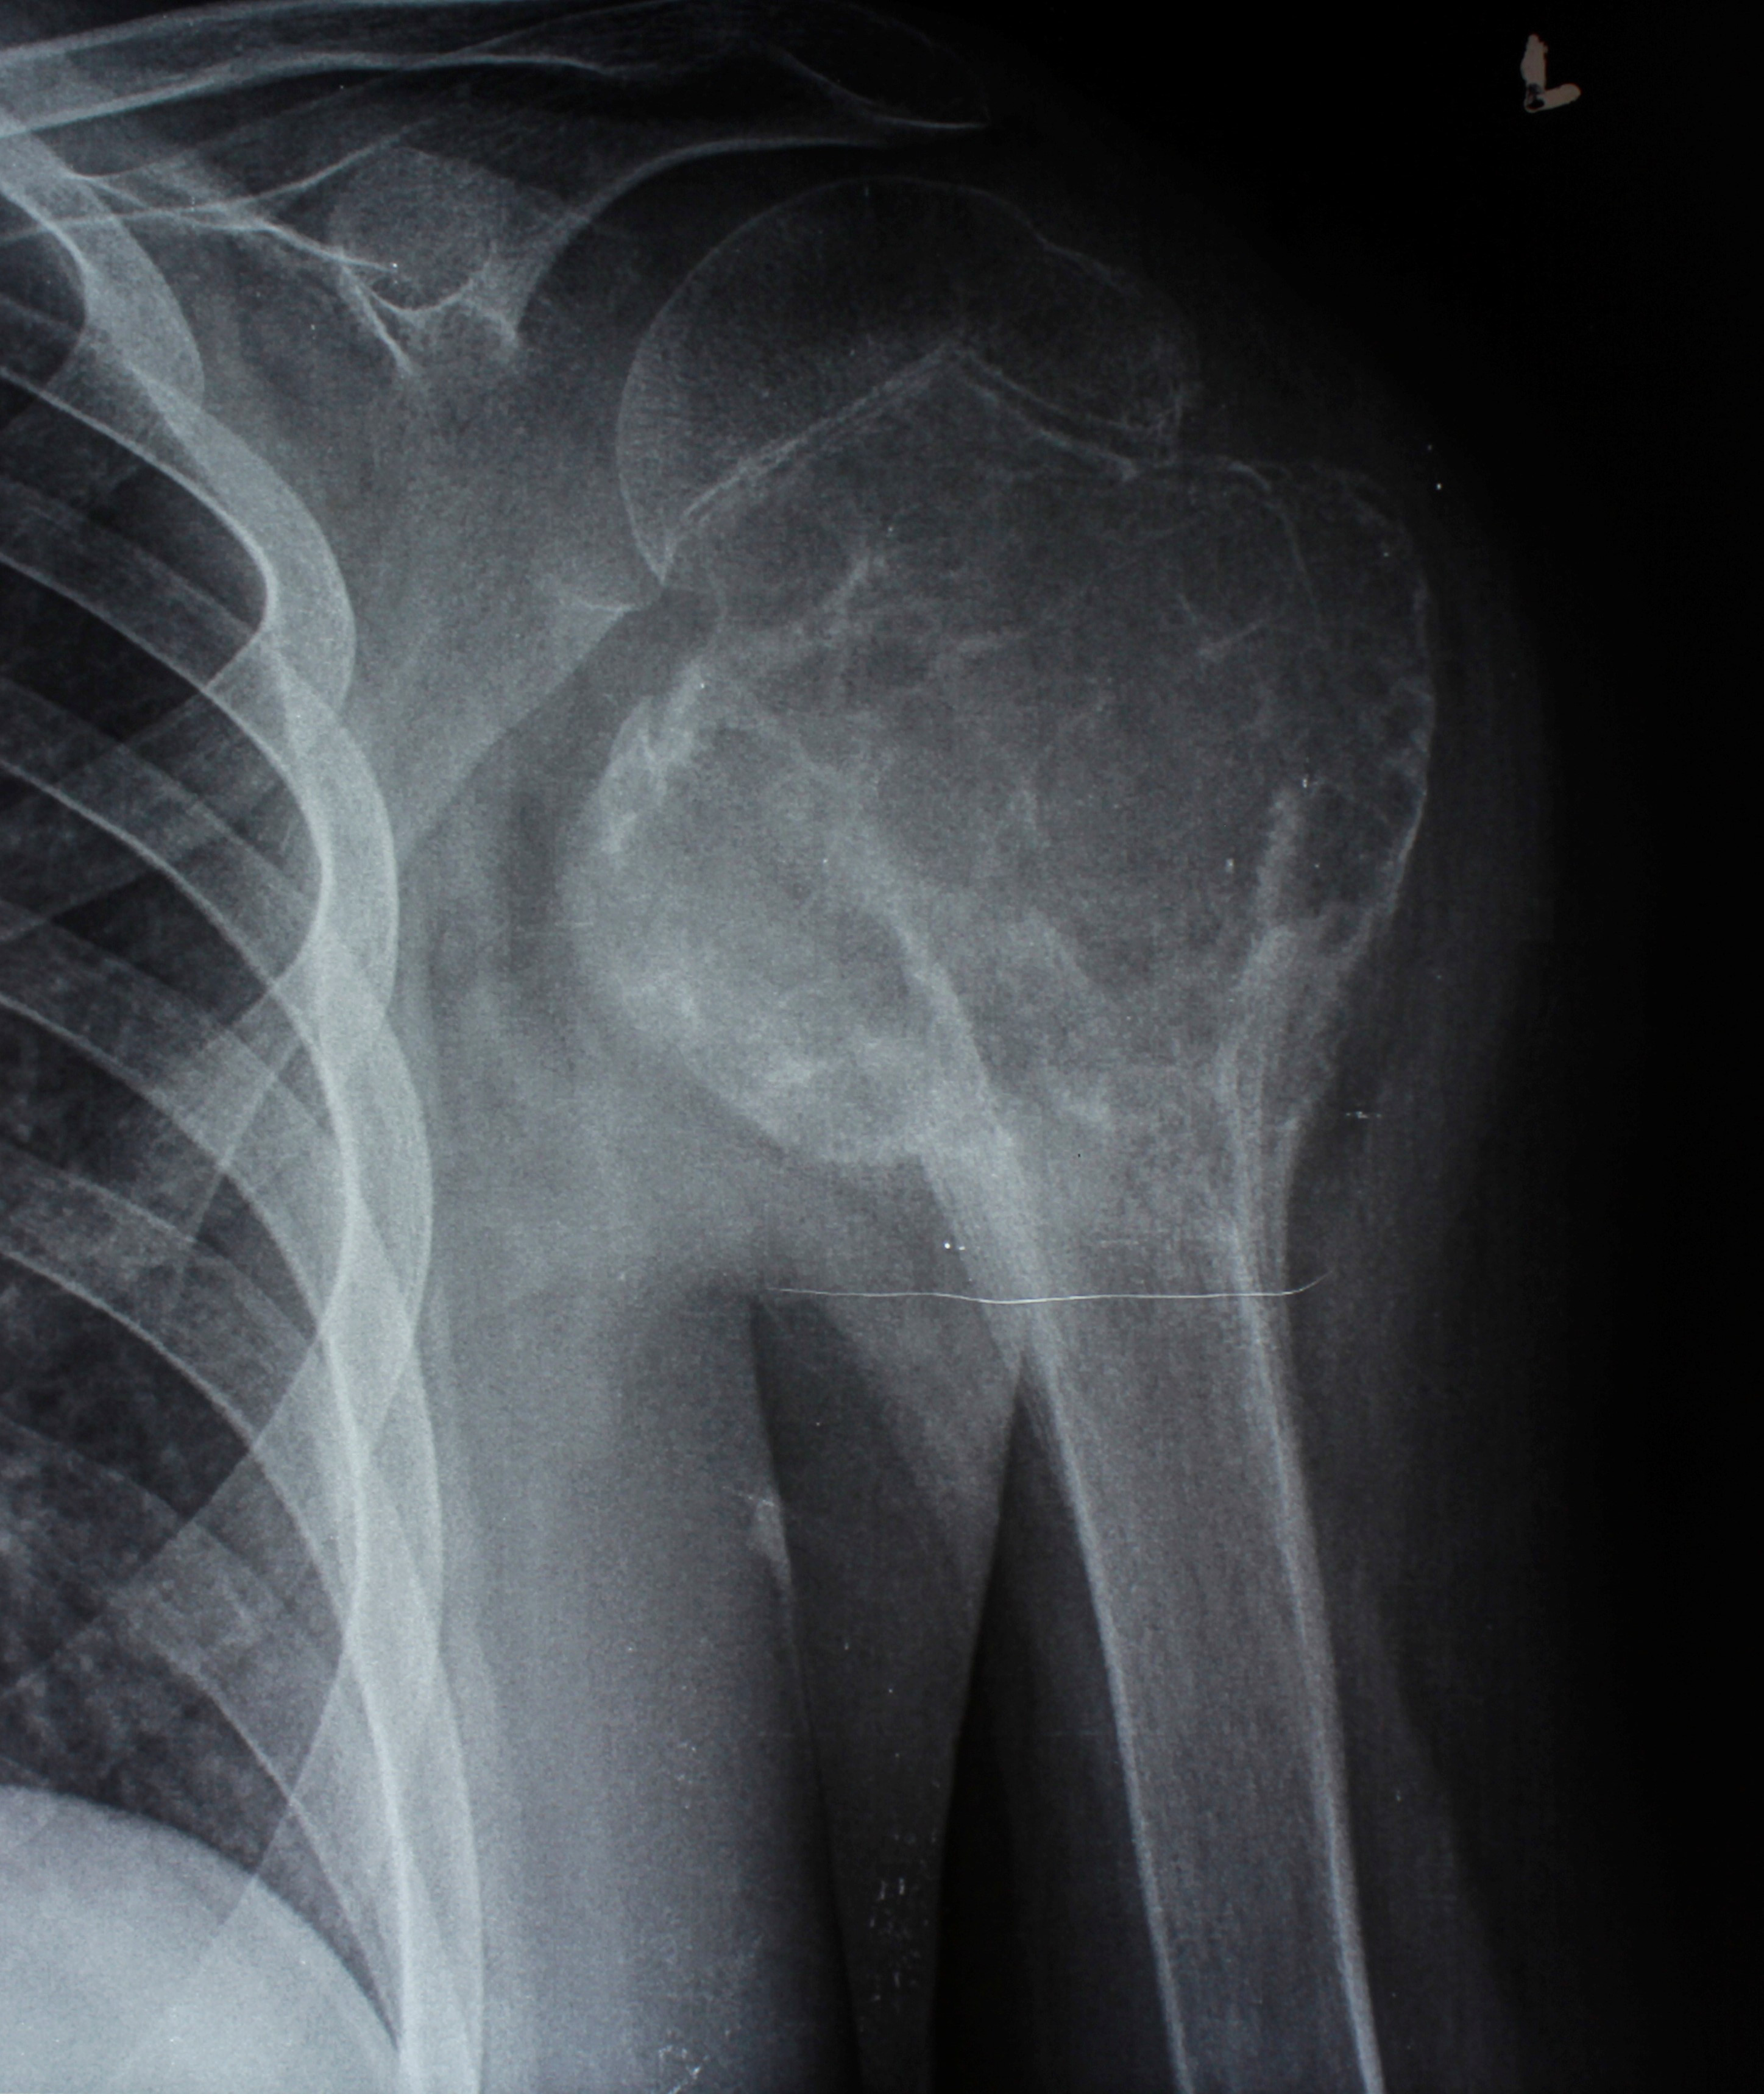

2. Բժշկական տարբեր կենտրոններում հետազոտվելուց հետո՝ 17-ամյա պատանին դիմել է «Նաիրի» ԲԿ։ Համապատասխան հետազոտություններ անցնելուց հետո՝ բուժառուի մոտ հայտնաբերվել է ոլոքի օստեոսարկոմա (ոսկրային քաղցկեղ): Նախավիրահատական բուժում ՝ քիմիոթերապիա, ստանալուց հետո՝ «Նաիրի» ԲԿ ում կատարվել է օրգանապահպան վիրահատություն : Հեռացվել են ծնկահոդն ու ոլոքի վերին երորդականը: Առաջացած դեֆորմացիան շտկել է Եվրոպայից պատվիրված էդոպրոթեզով, որը հնարավորություն է տվել պահպանել վերջույթի գործառույթը՝ քայլել, վազել և այլն։ Հետվիրահատական շրջանում բուժառուն ստացել է քիմիոթերապիա։ Այժմ գտնվում է բժիշկների հսկողության ներքո։

Վիրահատությունից առաջ